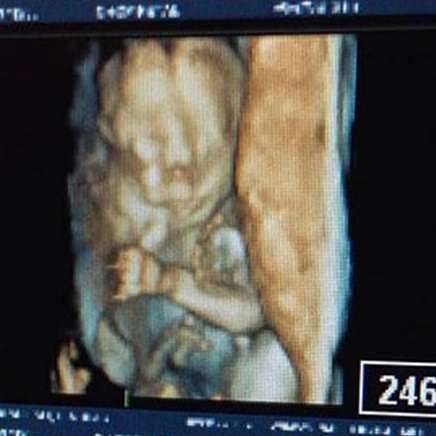

「无论如何,我们都希望能拥有她。」琳赛表示,他们决定等到欧玛拉27週大的时候,交给医生动手术,让他可以除去肿瘤,增加宝宝的生存机会。

由于27週时宝宝的肿瘤已经很大了,所以欧玛拉必须经由EXIT(ex utero intrapartum treatment)手术来切除肿瘤;这种手术是让胎儿维持脐带相连的状况,为妈妈剖腹,让他从子宫中出来接受手术,琳赛说:「这就相当于风险更高的一种堕胎。」

这个手术对欧玛拉的存活是必要的,但同时琳赛也必须面临着从此不孕的风险。他们决定尝试,因为只要手术顺利进行,欧玛拉就能留下来。